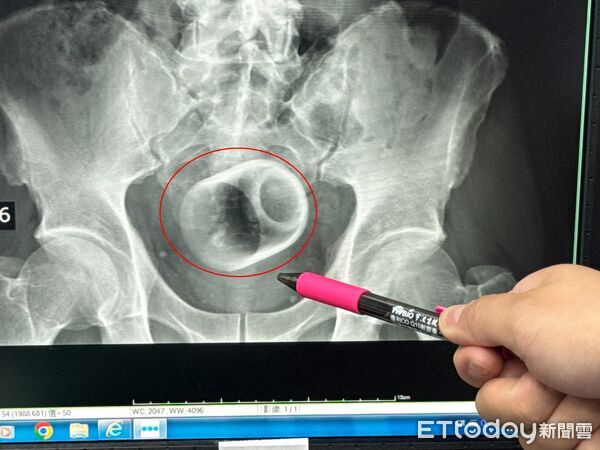

中部一名男子腹脹三天無法大便,肚子痛到受不了,趕緊到李綜合醫院求診,醫師透過X光檢查,驚見患者的肛門竟然塞一個直徑約6公分、高約8公分的陶瓷杯,原本要用器械夾出杯子,但杯緣光滑無法施力,杯子全被大腸包住,部分腸子缺血也造成壞死,最後全身麻醉「開腸破肚」的才順利取出杯子。

▲▼台中男子3天無法解便,竟是肛門塞了瓷杯。(圖/李綜合醫院提供,下同)